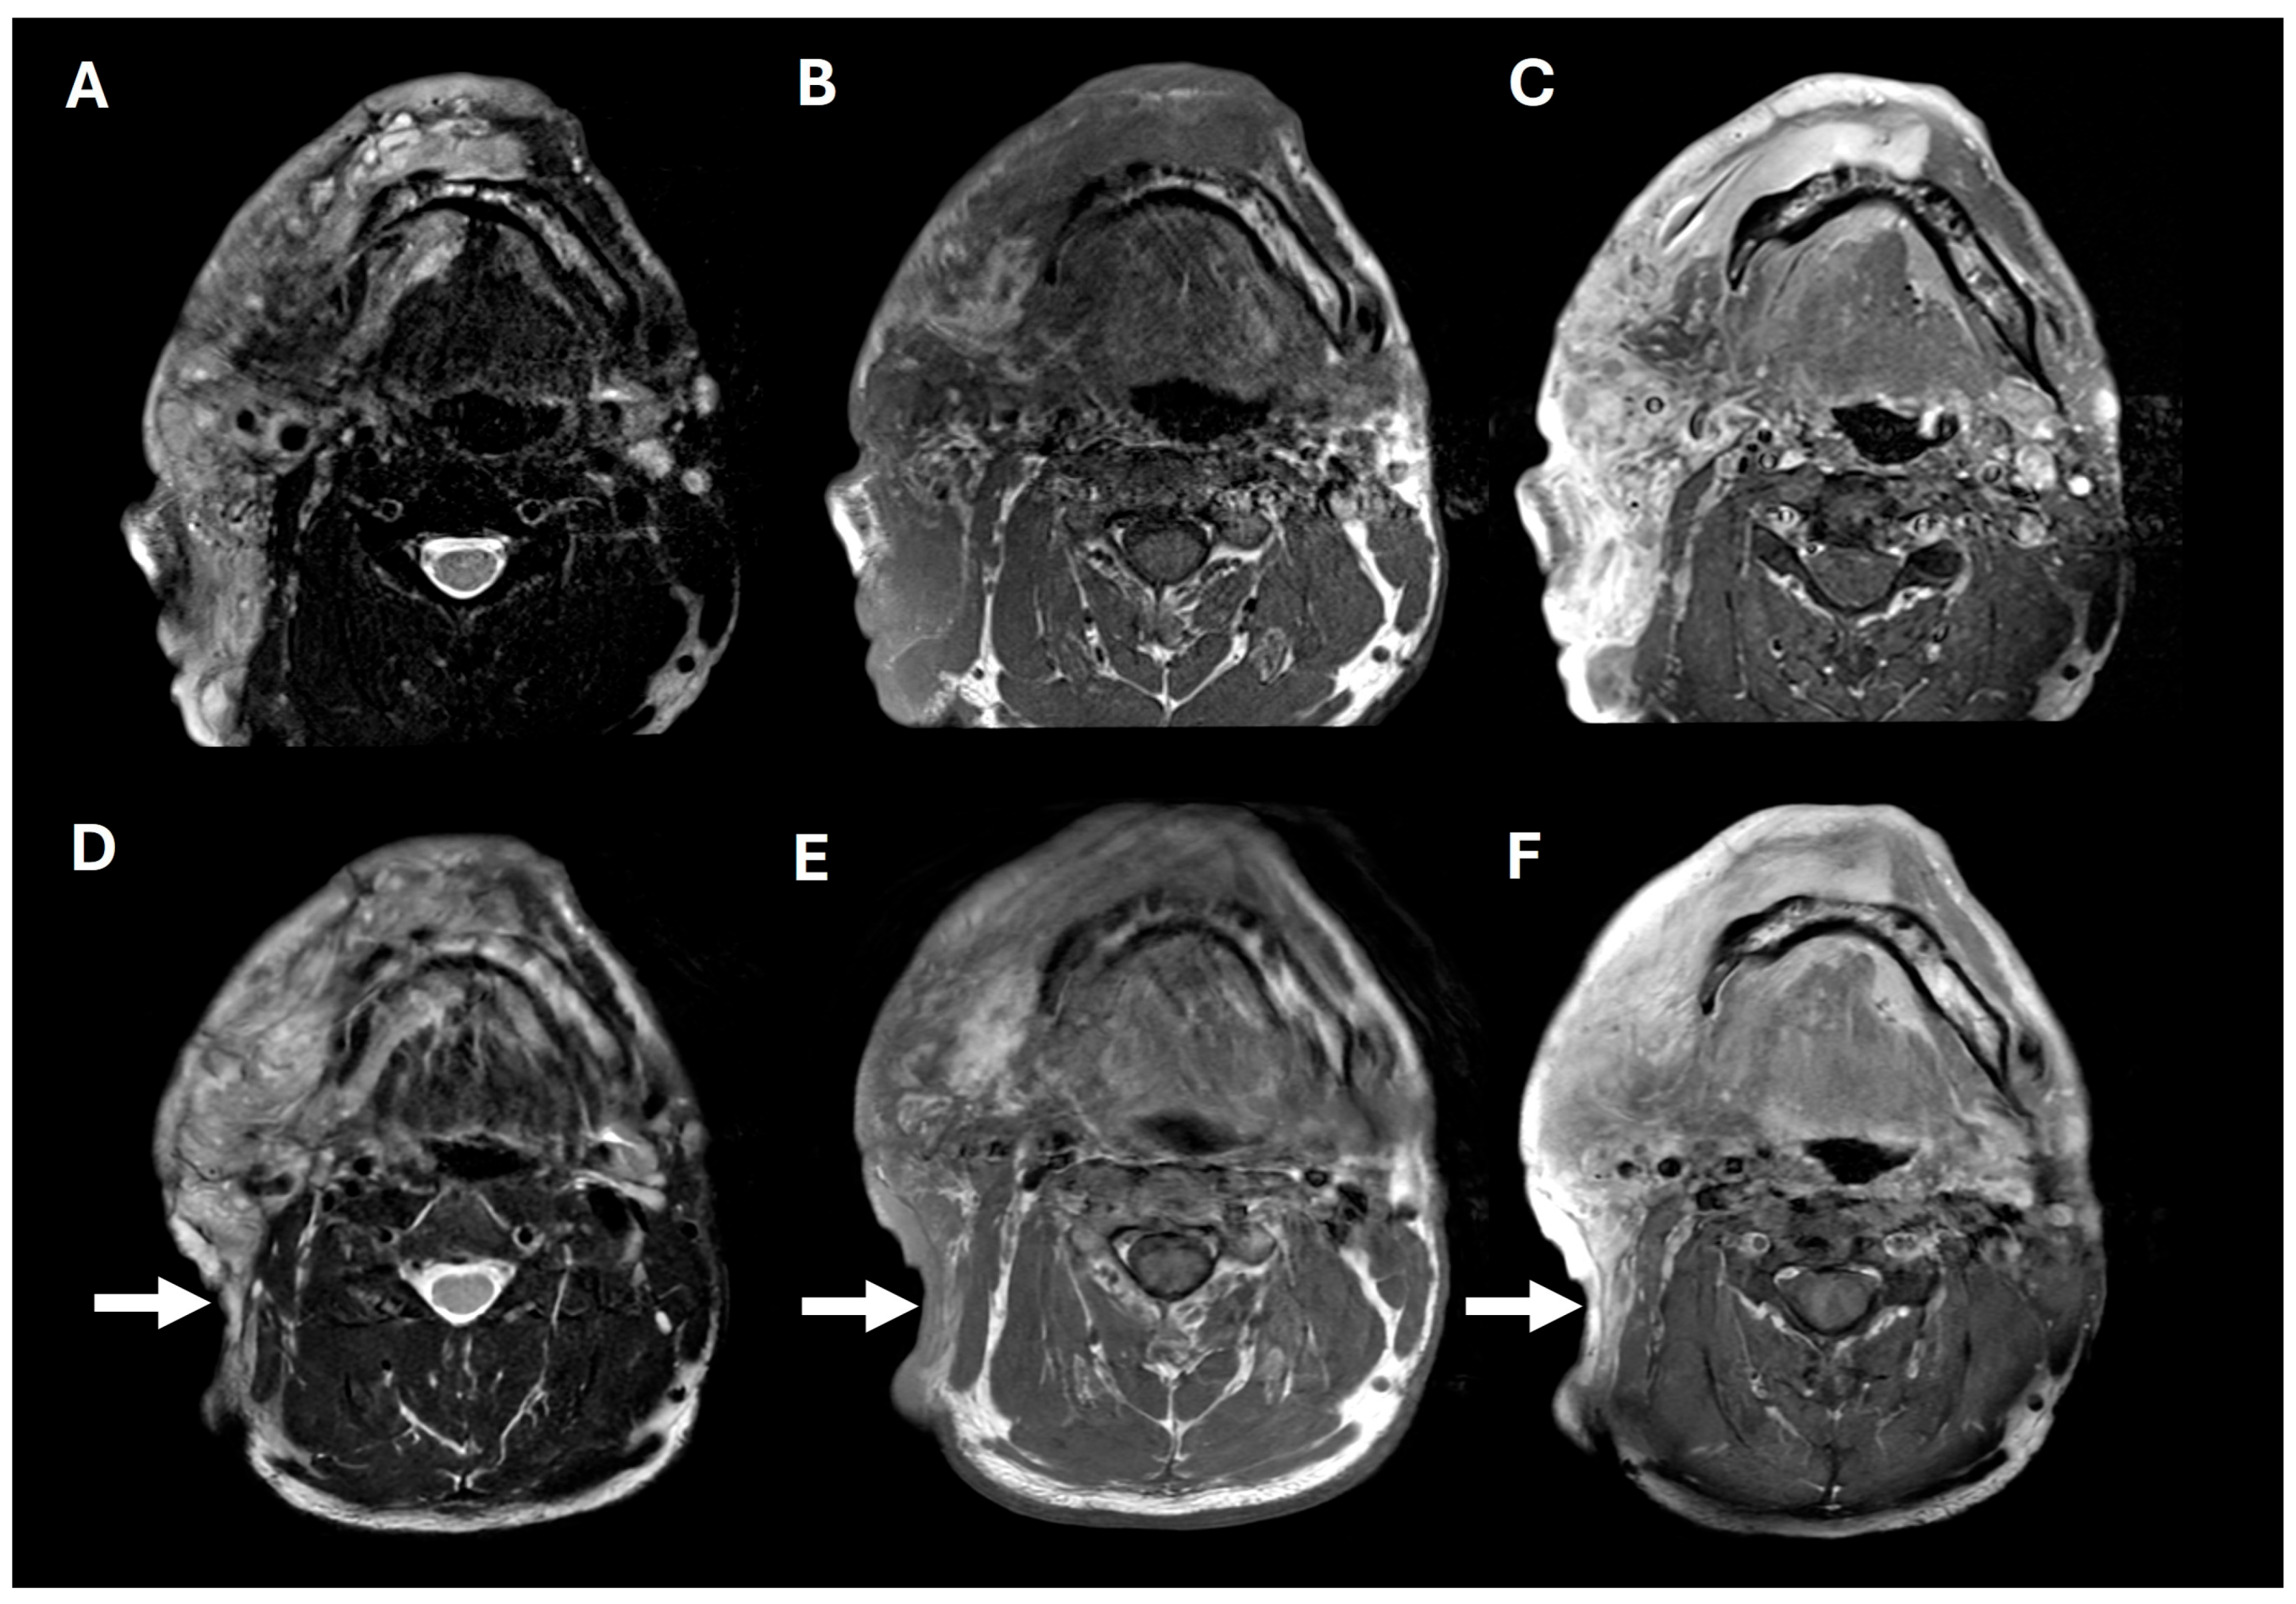

2. Case Presentation